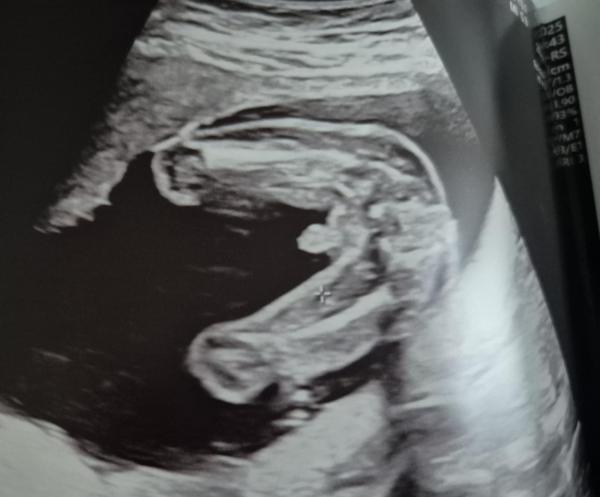

Hallo :) ich habe von meiner Frauenärztin bei 16+6 die Vermutung Junge bekommen und dieses Bild- denkt ihr das anhand des Bildes auch? Freue mich über Meinungen:)

Ich sehe da nichts "kaffeebohnenmäßes" und würde daher auch zum Jungen tendieren. :)

Ich denke, deine Gyn wird es am besten beurteilen können. Man sieht auf dem Bild glaub ich die Hoden von unten. Bei meinem Sohn sah es bei 20+4 so aus, er hat sich allerdings schon in der 14. SSW  zu erkennen gegeben und der NIPT hat es bestätigt 😊 .

Danke für die Antwort:) ja bei dir ist es wirklich eindeutig 😁 wo denkst du denn sind die Hoden in meinem Bild? 🤔

Hmm... das, was da so nach einem penis aussieht, ist im vergleich zu den Oberschenkelknochen viel zu groß. Deshalb finde ich es anhand des Bildes nicht eindeutig.